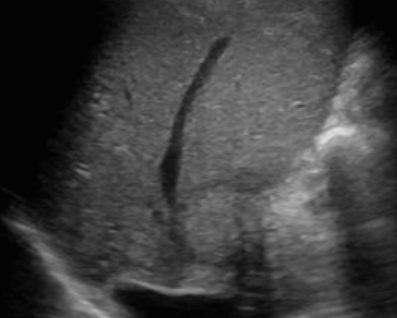

- 담석이 관찰되지 않고 간외, 간내담관의 확장소견을 시사하는 엽총징후(shotgun sign)이나 평행관 징후(parallel channel sign)가 관찰되기도 한다.

- 엽총징후(shotgun sign): 간외 담관이 확장되어 간외 담관과 문맥이 이웃해 관찰된다.

- 평행관 징후(parallel channel sign): 간내 담관이 확장되어 인접하고 있는 문맥과 나란히 2개의 관상구조로 나타난다.